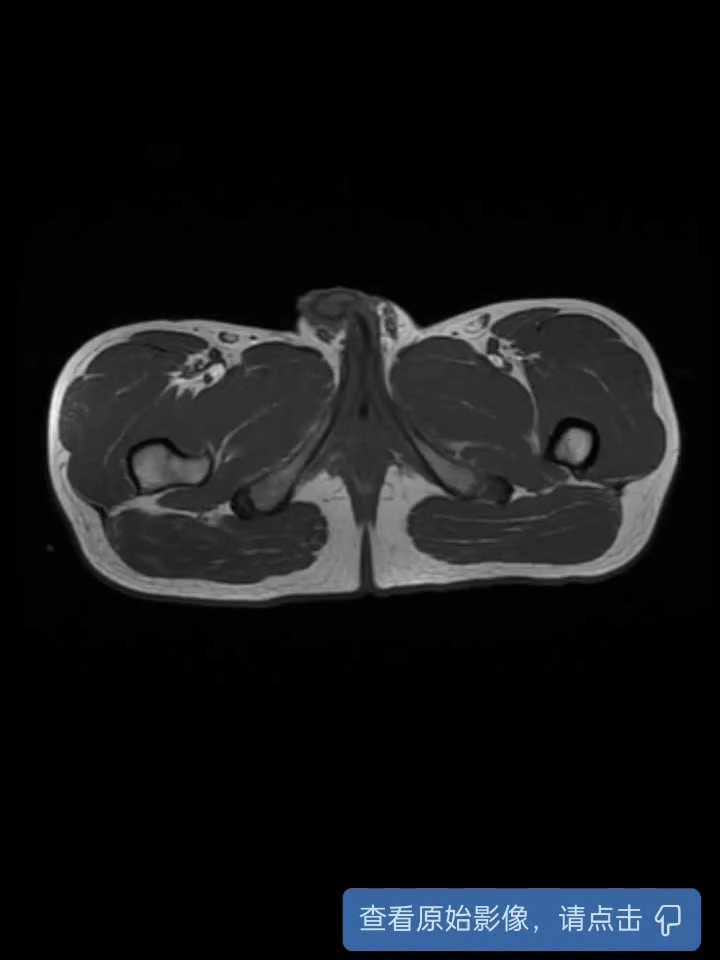

盆腔增强CT

磁共振增强